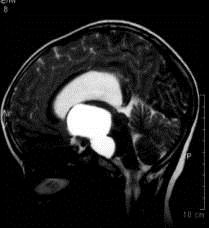

问题 病历摘要:??患者女性,6岁,半年来感觉视力模糊,近10天出现反复头痛,间有恶心呕吐,精神转差,查体:神志清楚,身高90cm,体重25Kg,血压90/55mmHg,右眼视力4.6,左眼视力4.8,双侧视乳头水肿,颈软,伸舌居中,四肢肌张力正常,肌力5级,双侧Babinski征(-)。 该患者就诊时,应作那些必要的检查?